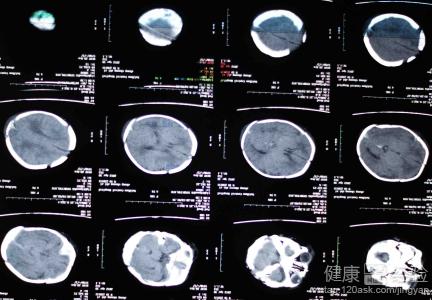

新生兒缺氧缺血性腦病的程度有多嚴重

新生兒缺氧缺血性腦病要引起大家的重視,因為新生兒缺氧缺血性腦病是比較常見,且危害較重的一種疾病,它不僅會導致腦癱、癫痫等症,嚴重者還會導致死亡,它主要是在圍產期窒息導致腦的缺氧缺血性損害。一般分為輕度、中度和重度。輕度患兒治療後無後遺症,但是中度新生兒缺氧缺血性腦病15%預後不良,重度新生兒缺氧缺血性腦病90%預後不良。

1首先,新生兒缺氧缺血性腦病它主要是在圍產期窒息導致腦的缺氧缺血性損害。生後即出現異常神經症狀並持續24小時以上。輕型患兒僅有激惹或嗜睡,重型意識減退、昏迷或木僵,並可出現瞳孔改變等腦干損傷表現。

2其次,一般來說新生兒缺氧缺血性腦病分為輕度、中度和重度三種類型。輕度患兒表現為:過度覺醒狀態、易激惹等。中度患兒表現為:抑制狀態、嗜睡或淺昏迷等。重度患兒表現為:昏迷狀態重度或為去大腦僵直狀態。

3最後,通常輕度患兒治療後無後遺症,但是中度新生兒缺氧缺血性腦病15%預後不良,重度新生兒缺氧缺血性腦病90%預後不良。病情危重者病死率高,幸存者可遺留各種神經系統後遺症,如腦癱、共濟失調、智力落後和癫痫等。